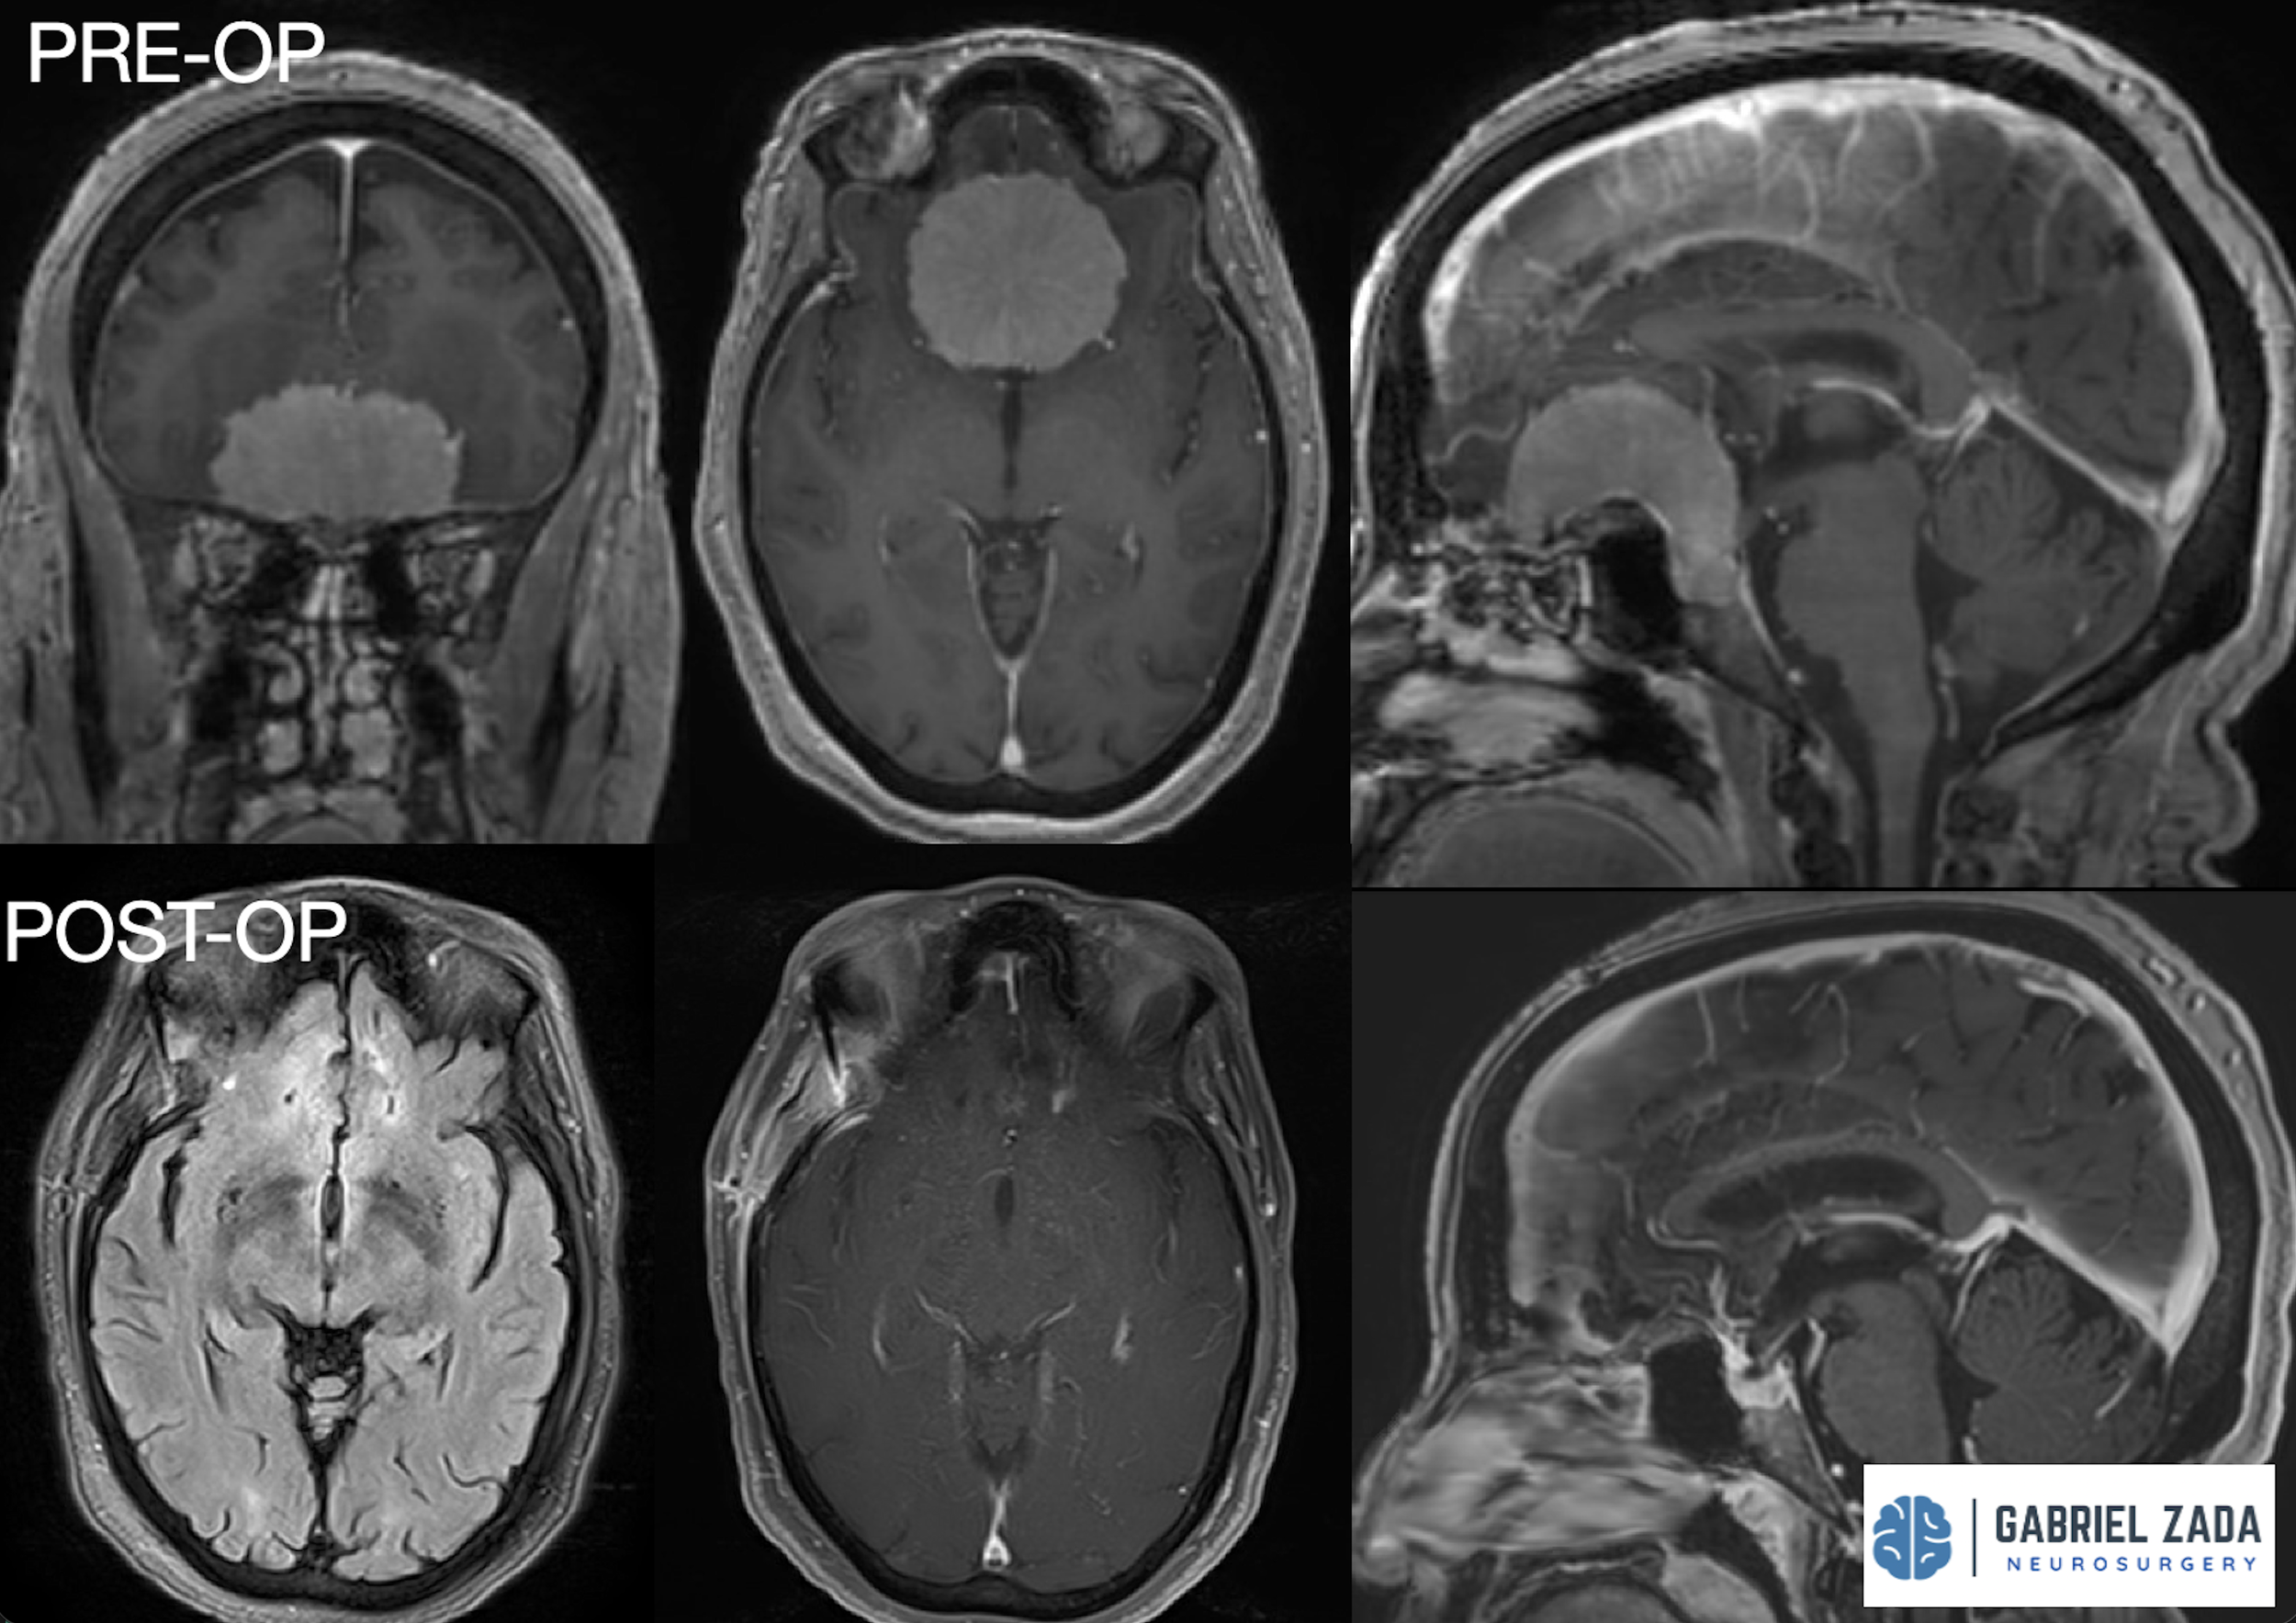

Explore this comprehensive gallery featuring pre‑ and post‑operative imaging of patients with skull‑base tumors treated by Gabriel Zada, MD, MS, FAANS, FACS. These cases highlight Dr. Zada’s expertise in advanced neurosurgical techniques and outcomes.

*Representative cases shown for educational purposes. All images de-identified. Individual results vary.